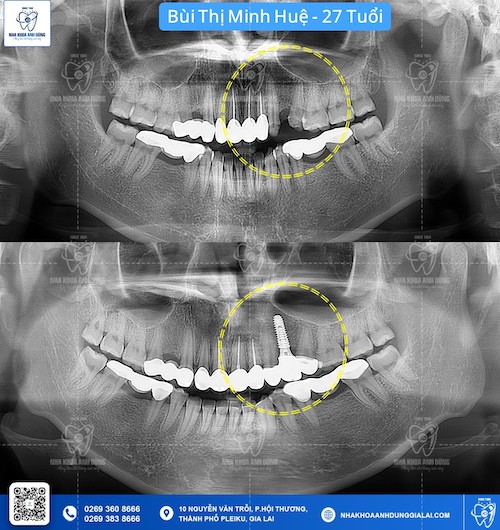

Vì những ảnh hưởng nêu trên, phương án nhổ răng kết hợp trồng răng Implant là sự lựa chọn lý tưởng nhất cho người bị mất răng. Đối với phương pháp này, sau khi nhổ răng, trụ Implant sẽ được đặt vào đúng vị trí mới nhổ đó bằng cách khoan nhẹ vào xương hàm để tạo một khoảng trống vừa đủ cho việc đặt trụ Implant. Sau thời gian lành thương và trụ Implant đã tích hợp vào xương hàm, bác sĩ sẽ gắn khớp nối để nối trụ Implant với mão răng sứ ở phía trên và tạo nên một chiếc răng hoàn chỉnh giống với răng thật.

- Về chất lượng của xương hàm: xương hàm tốt là đủ dày và chắc khỏe để có thể nâng đỡ trụ Implant. Bác sĩ sẽ chụp X-quang để đánh giá mật độ xương và đưa ra chỉ định phù hợp với từng tình trạng của khách hàng.